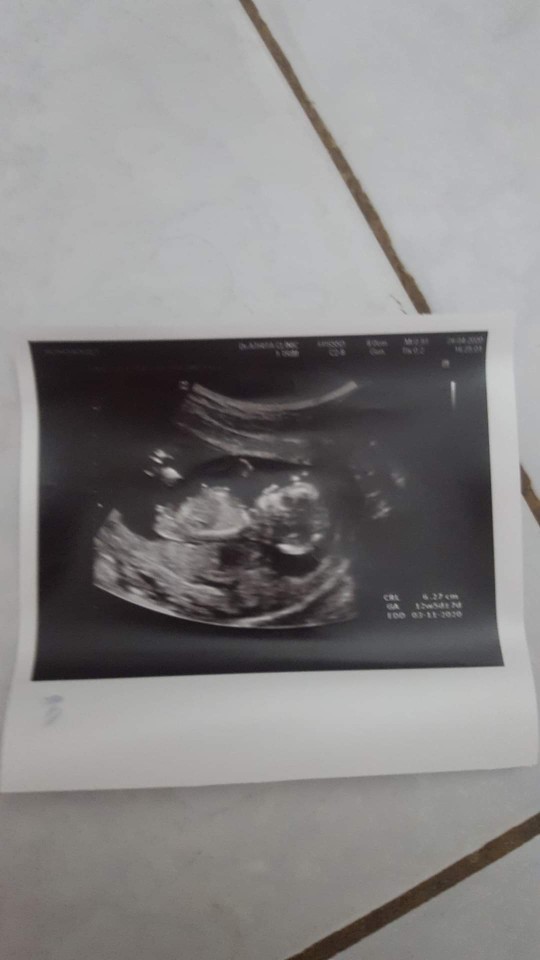

14 ธค ค่า♡